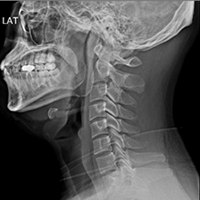

• Normal Cervical X-ray:

Gentle C-shaped

curve